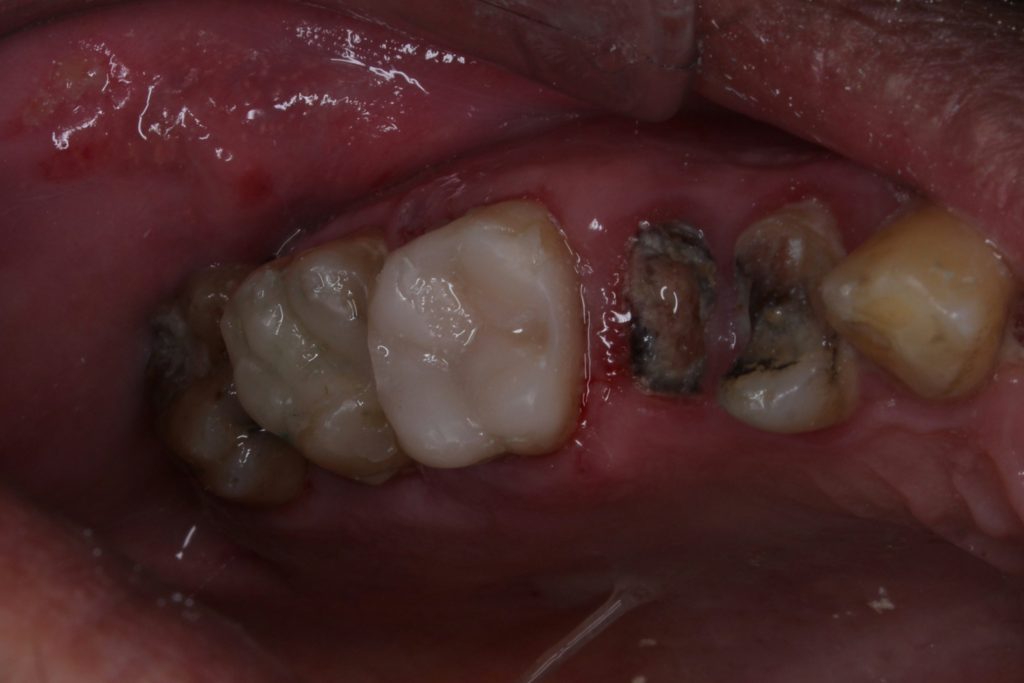

The patient presented with an old defective amalgam restoration on tooth U6. The restoration showed marginal leakage, discoloration, and secondary caries extending subgingivally on the distal aspect.

After local anesthesia and proper isolation with rubber dam, the old amalgam was carefully removed. Upon removal, deep margins were detected and all cavity walls were undermined, necessitating complete removal of unsupported enamel and defective dentin.